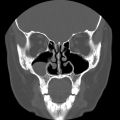

A CT Sinus exam is a fast, painless scan that captures very clear pictures of your sinus cavities. While a provider’s order is required for this exam, where you go is up to you. RAYUS centers throughout Puget Sound offer CT Sinus exams on multi-slice CT scanners run by certified technologists, typically with rates that are 30 – 50% less than if you had the same exam at a hospital-affiliated imaging provider.

The CT Sinus exam allows our subspecialized radiologists to look at different levels of the skull and sinus cavities to review for:

- Injury, trauma

- Infection, inflammation

- Fluid level issues

- Abnormalities, growths/polyps, deviated septum

- Pre-surgical planning

The CT technology allows us to see the issues behind your symptoms much more clearly than X-ray or with an endoscope, especially when evaluating the ethomid and sphenoid sinuses which sit behind the frontal and maxillary sinuses.